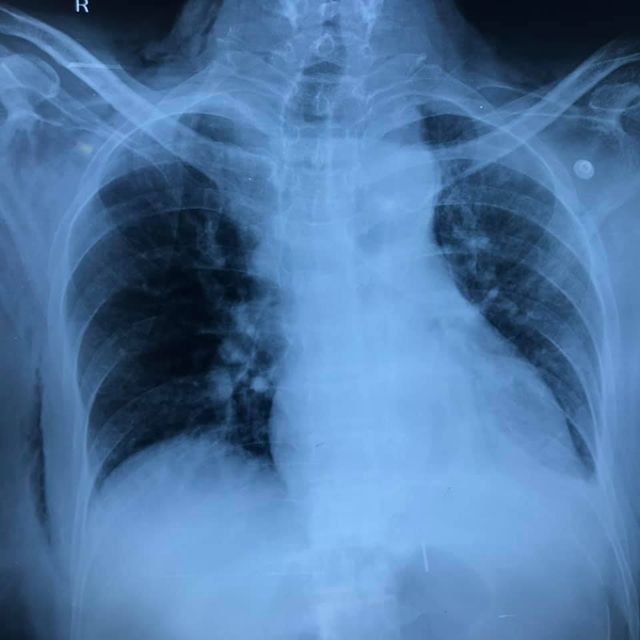

51 yr old patient with recurrent vomiting and dyspepsia and left sided chest pain. CT, Barium showed fundus and body of stomach in thoracic cavity with Mesentroaxial Volvulus. (image 1-4) Pre-OP thought to be a large sliding paraesophageal hernia operative findings revealed a posterior defect separate from hiatus suggestive of Bochdalek diaphragmatic hernia with a small hiatal hernia. Repair of Bochdalek defect with Crural repair was performed with mesh reinforcement. A 270 degree fundoplication was added (instead of a 360 as Manometry could not be performed preoperatively) (image 6-10) postoperative recovery was smooth (preop-postop xrays image 11-12).